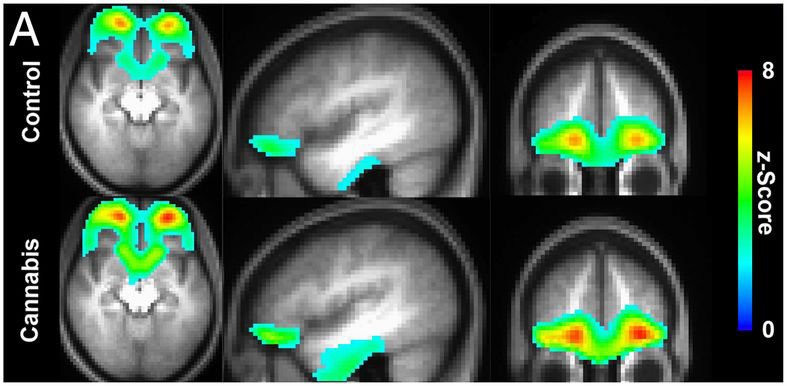

Tras haber obtenido imágenes por resonancia magnética funcional de la corteza orbitofrontal los científicos del siguiente estudio, publicado en la revista 'PNAS' concluyeron que esta región del cerebro se hace más pequeña en las personas que fumaban cannabis durante años, mientras las interconexiones de algunas partes aumentan.

Así en el modelo B se observa la actividad extra de la corteza orbitofrontal de una persona que fuma marihuana, la cual no está presente en elmodelo A de una persona que no consume.